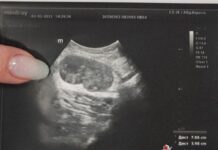

Врачи Центральной городской больницы №7 Екатеринбурга совершили настоящий прорыв, удалив пациентке гигантскую миому матки весом 15,4 кг. Сложнейшая операция стала шансом на новую жизнь для 44-летней женщины, которая в течение четырёх месяцев страдала от сильных болей в животе, одышки, тошноты и резкого снижения веса. Обследование показало, что масштабное новообразование в области малого таза и брюшной полости вызвало непроходимость кишечника, потребовавшую экстренного вмешательства.